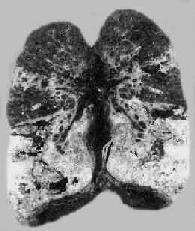

3.慢性纤维空洞型肺结核为成人慢性肺结核的常见类型,多在浸润型肺结核形成急性空洞的基础上发展而来。病变特点是在肺内有一个或多个厚壁空洞形成。同时在同侧肺组织,有时也可在对侧肺组织,特别是肺下叶可见由支气管播散引起的很多新旧不一、大小不等、病变类型不同的病灶,部位愈下病变愈新鲜。空洞多位于肺上叶,大小不一,呈不规则形,洞壁厚,有时可达1cm以上。洞内常见残存的梁柱状组织,多为有血栓形成并已机化闭塞的血管。空洞附近肺组织有显著纤维组织增生和肺膜增厚(图18-8)。镜下,洞壁分三层:内层为干酪样坏死物质,其中有大量结核杆菌;中层为结核性肉芽组织;外层为增生的纤维组织。由于病情迁延,病变广泛,新旧不等,肺组织遭到严重破坏,可导致肺组织的广泛纤维化,最终演变为硬化型肺结核,使肺体积缩小、变形、变硬、肺膜广泛增厚并与胸壁粘连,可严重影响肺功能。

慢性纤维空洞型肺结核病(冠状切面)

图18-8 慢性纤维空洞型肺结核病(冠状切面)

右上叶,左上叶上部和左下叶上部都有厚壁空洞形成;肺门淋巴结无结核病变